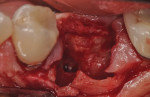

The patients were referred for the placement of dental implants to a clinical private practice limited to periodontics and dental implants. Informed consent was obtained prior to treatment. Anesthesia was obtained with local infiltration using articaine 4% with 1:100,000 epinephrine, except in those patients where this could not be tolerated and carbocaine 2% with 1:20,000 levonordefrin was used. Sulcular incisions were performed around the tooth to be extracted and were minimally extended to the adjacent teeth to mobilize the flap. Teeth were extracted using elevators and extraction forceps. In situations that were more challenging, a piezoelectric handpiece (Piezotome 2™, ACTEON North America, www.acteongroup.com) or dental high-speed handpiece were used to free up the root that was in the socket. Upon the tooth’s removal, the socket was curetted thoroughly to remove any residual soft tissue, and the socket was inspected to see whether it was intact (Figure 1). If the buccal or lingual plates were lost in any way, the flap was extended to provide better access to and visualization of these areas. The sockets were irrigated with povidone iodine for approximately 1 minute to further reduce any residual bacterial contamination of the site and then rinsed of this agent by copious use of sterile water.